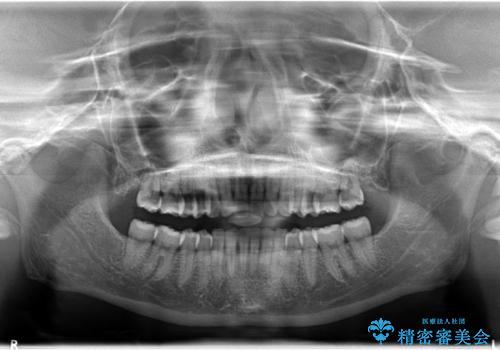

Invisalign インビザラインによる軽度なガタつきの改善

- 奥歯の位置関係はそこまで大きくいじらず、前歯群のみでガタつきの改善を計画しました

奥歯の位置関係に改善の余地はありますが、機能的に問題のない cusp to fossa の関係で咬めているため、前歯のガタつきを前歯のみで改善するというシンプルな計画で、短期間で治療を終了させました。